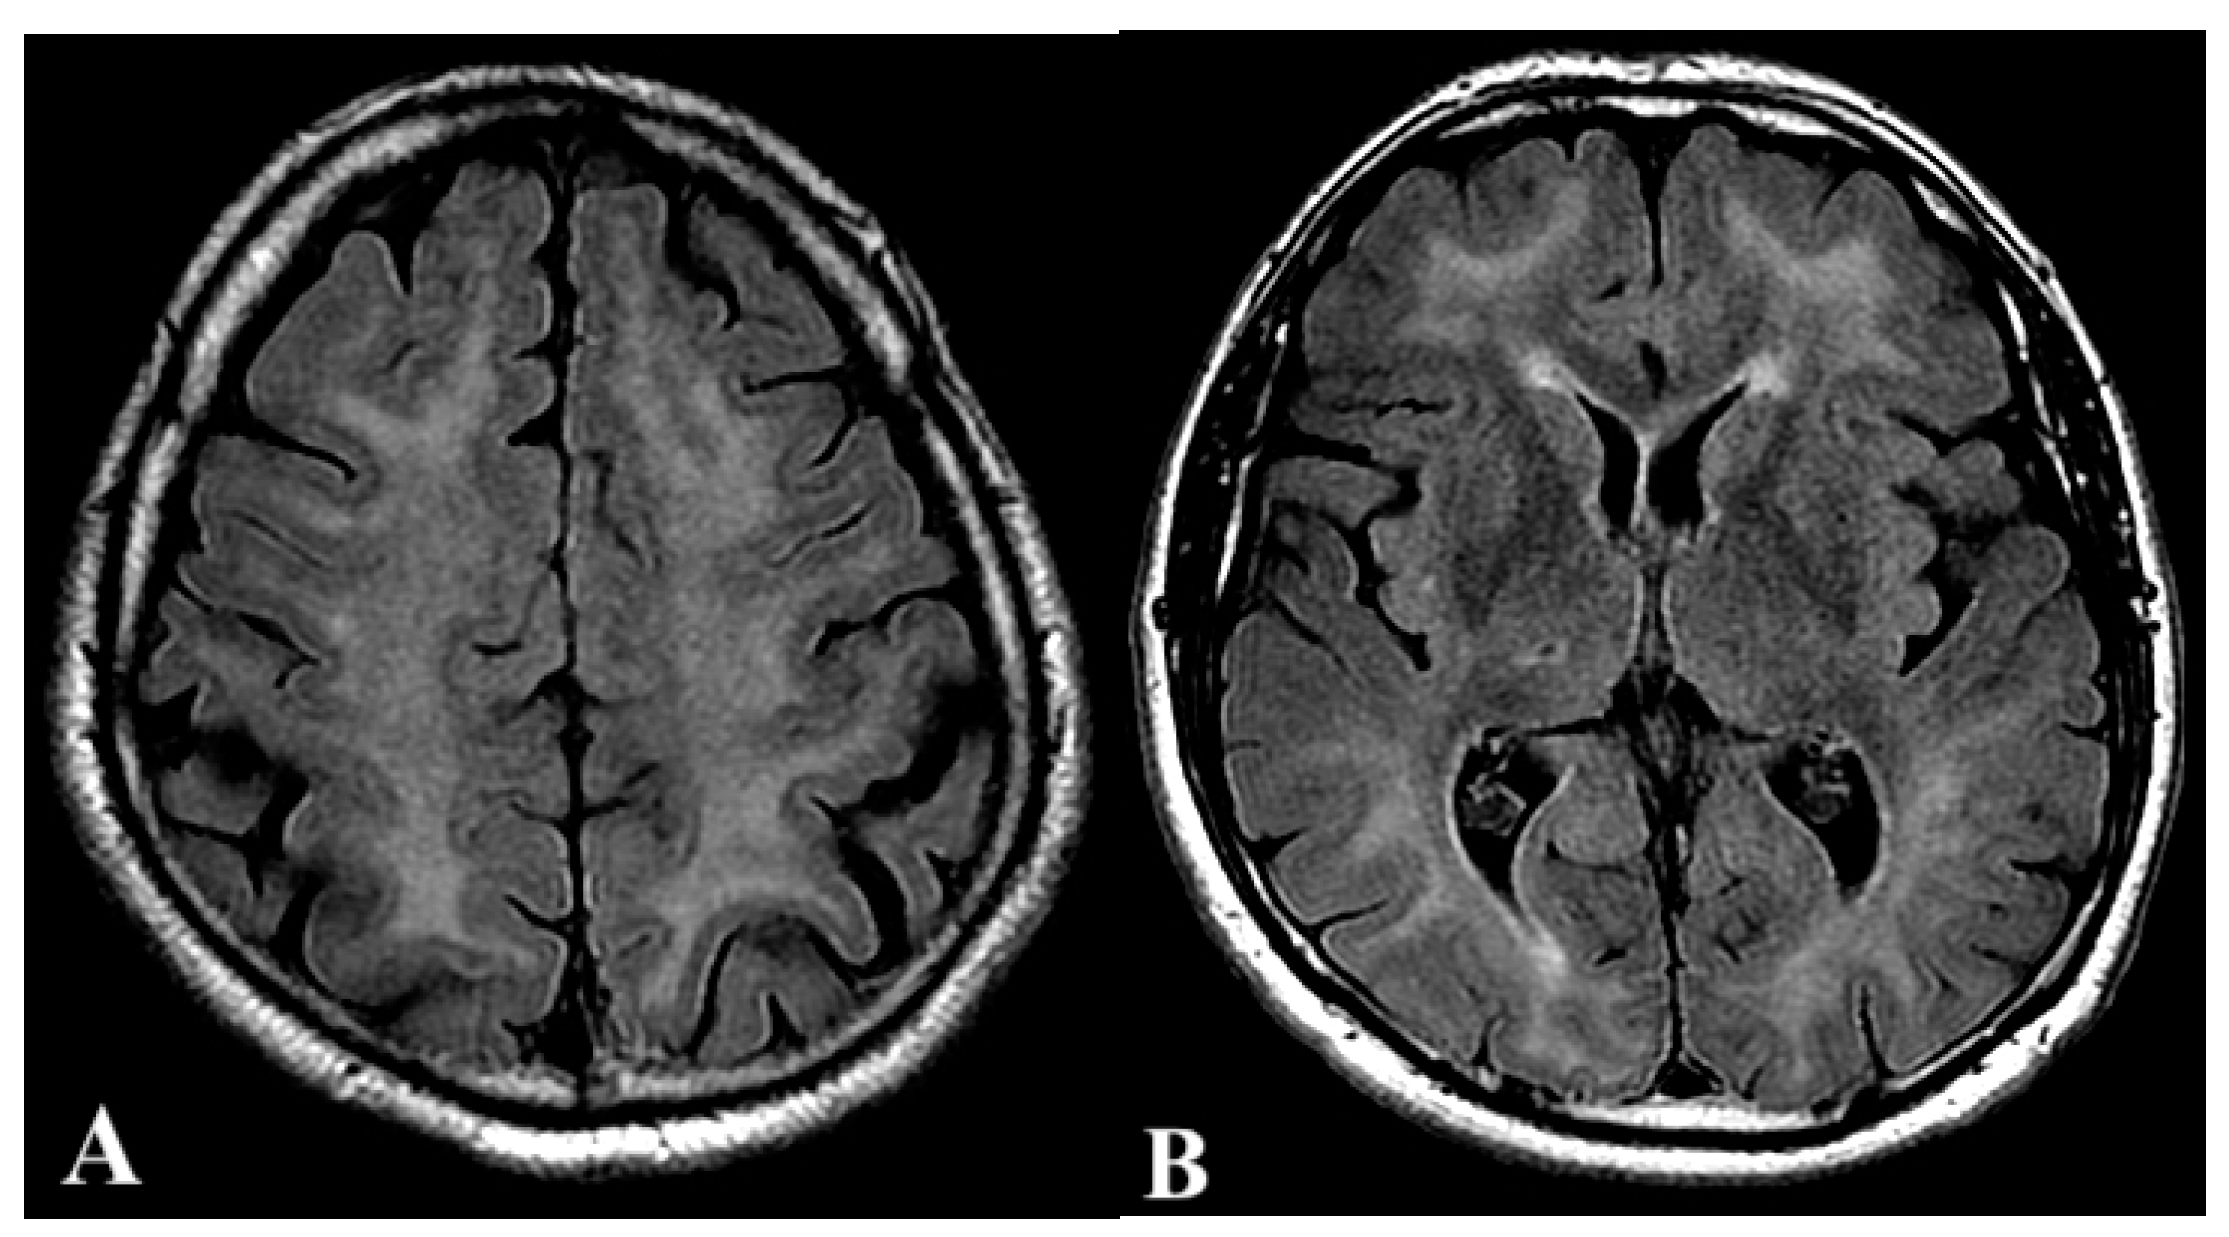

2.2. Second Case